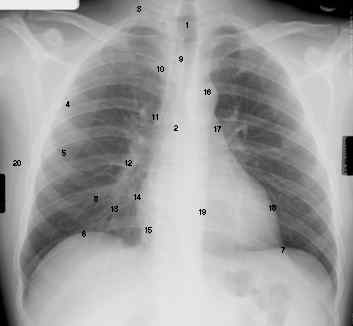

Features of anatomy visible on normal PA film

1.Tracheal air column

2.Carina

3.First rib; count down from here for diaphragmatic level

4.Peripheral 1-2 cm of lung fields have no markings except

5.The minor fissure

6.Top of the diaphragm is near the medial half of its length. The top of the right diaphragm is normally at a level between

the anterior end of the anterior 6th rib and the anterior 7th rib. The level of the diaphragm can also be reported eith

reference to the posterior ribs: on full inspiration, the domes of the diaphragm are seen overlying the posterior aspects fot

he 10th and 11th ribs.

7.Left diaphragm is lower in 90-95% of normals by roughly half an interspace (2% greater than 3 cm)

8.Inferior margins of the posterior ribs are often ill-defined

9.Anterior mediastinal line (apposed visceral and parietal pleura of the two upper lobes

10.Superior vena cava shadow blends imperceptibly into the shadows of the neck

11.Region of the azygous vein (vein not visible). A caliber greater than 7 mm is suggestive of raised venous pressure, or

enlargement of adjacent node. Normal may be up to 10 mm.

12.Right descending pulmonary artery. Not greater than 16 mm in men, 15 mm in women

13.Pulmonary arteries and veins. Hard to distinguish the two. Arteries are vertical and medial and emerge from the hilum.

Veins are horizontal and lateral ad run toward the left atrium below the hilum.

14.Border of the right atrium

15.Inferior vena cava

16.Aortic arch

17.Left pulmonary artery

18.Border of the left ventricle

19.Descending aorta

20.Fat density lines in the intermuscular fascial layers